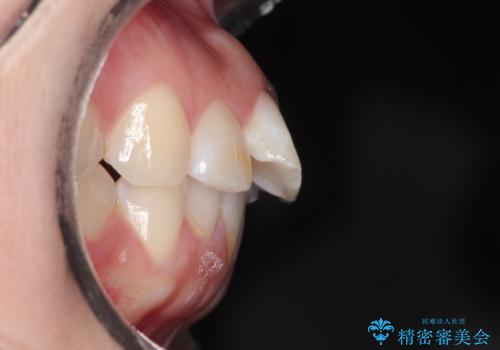

【インビザライン】前歯が出ているのを治したい

- 前歯が出ていることを主訴に来院されました。

前歯の突出感が改善され、満足していただきました。